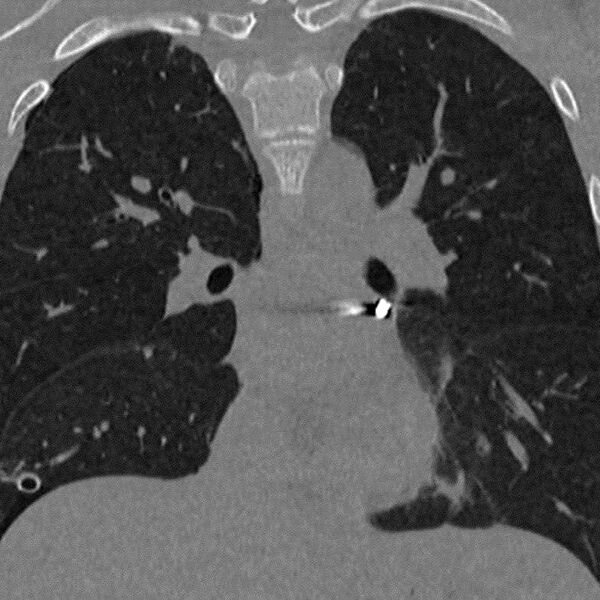

«Инородное тело мигрировало в опаснейшую зону — между легочными венами у задней поверхности предсердия. Мы выполнили малоинвазивную операцию со вскрытием перикарда, работая буквально в миллиметрах от жизненно важных структур», — рассказал заведующий отделением детской хирургии № 2 Никита Степаненко.